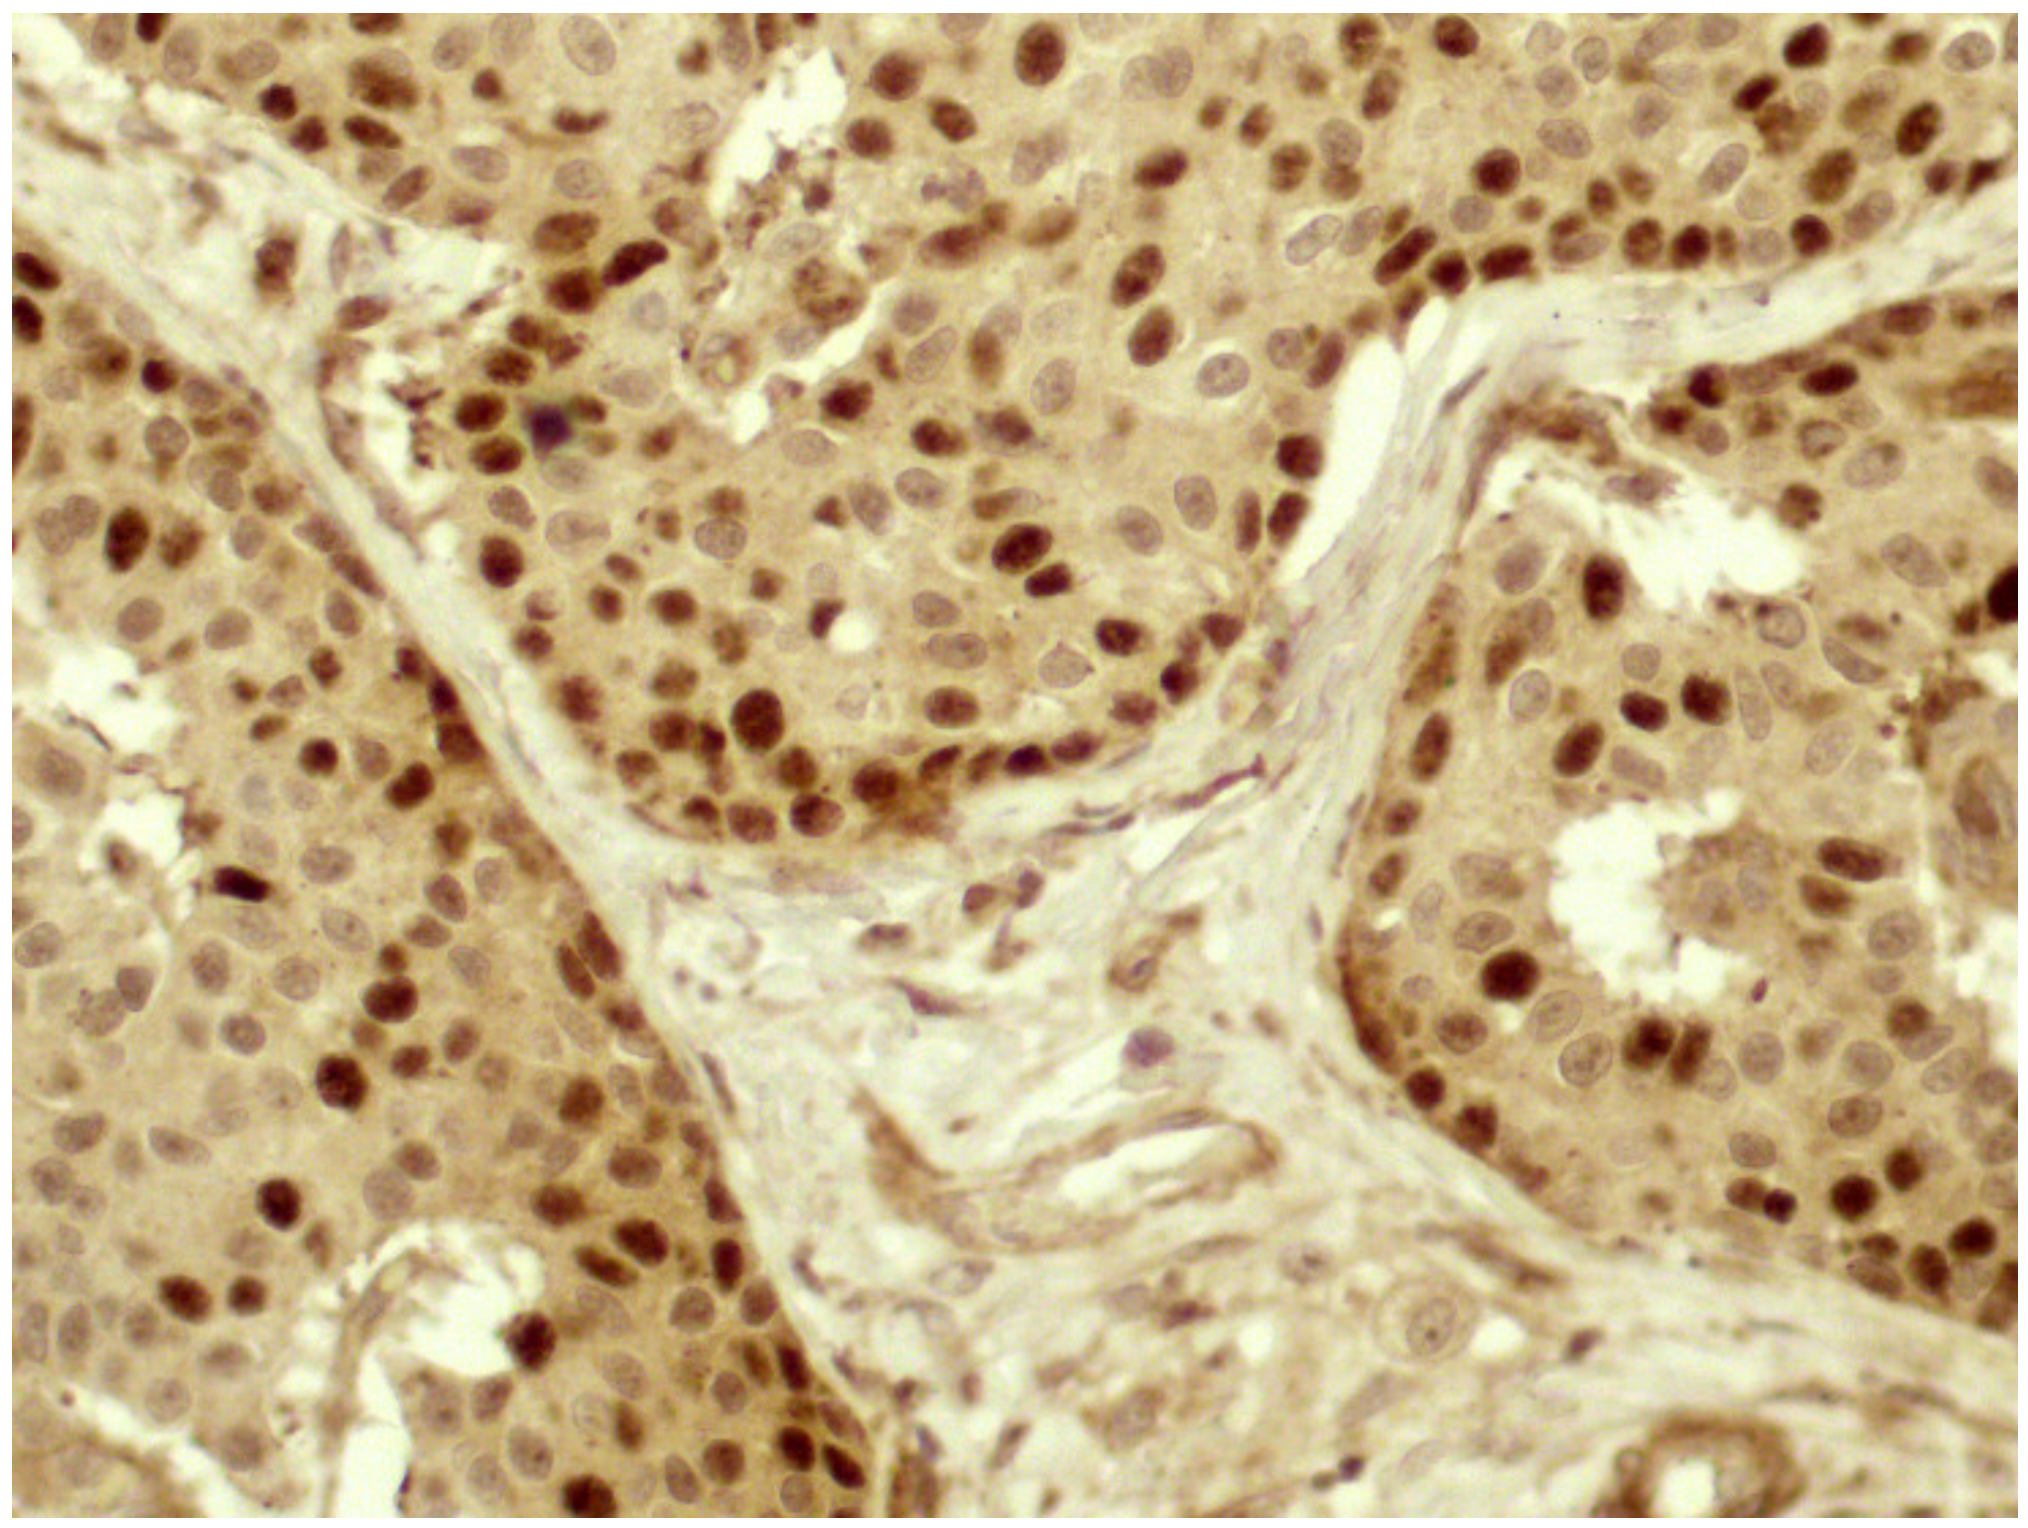

In most cases, especially in well-differentiated tumors, the signal was stronger at the periphery of neoplastic nests (Figure 2), where the epithelial cells were in contact with the surrounding stroma.

Figure 2.

In most cases, Twist reactivity was located mainly at the periphery of the neoplastic nests, at strict contact with the stroma (40× magnification).